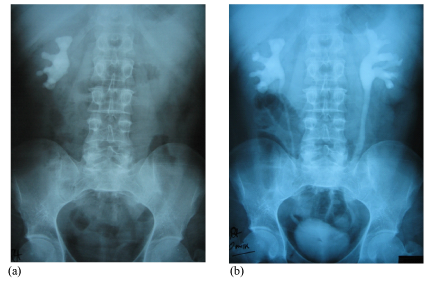

A 40year old male patient was admitted with symptoms of Bi lateral loin pain. Radiological investigations revealed a 1.2cm calculus in the left lower ureter with hydroureteronephrosis and a complete branched Staghorn calculus occupying the entire collecting system with moderate hydronephrosis in the right kidney (Figure 1a & 1b). Routine pre operative investigations including Renal function test and metabolic work up for stone disease was normal. Urine routine showed microscopic haematuria and culture was negative. The patient was first taken up for Ureteroscopy for the left lower Ureteric calculus. The stone was fragmented using Lithoclast and removed and a Double ‘J’ stent was inserted. Two weeks later he was taken up for a Modified Anatrophic Nephrolithotomy for the Right Staghorn Calculus. A preliminary Cystoscopy, RGP and a double J stent insertion was done on the right side. The left side stent previously placed during Ureteroscopy was removed. The patient was placed in the left lateral position and a Rt. loin incision made through the bed of 11th rib excising the terminal segment of the rib. The Gerota’s fascia was opened and the Right Kidney was mobilized completely (Figure 2a). The Renal artery was carefully dissected well away from the hilum to avoid arterial spasm that may occur during dissection close to hilum of the kidney and taped with Vesiloop (Figure 2b). Ice slush was prepared from frozen Ringer lactate solution. A water proof sterile sheet was taken and a central opening made to allow only the kidney to pass through. 100ml of 20% Mannitol was infused quickly. The kidney was turgid and there was a good urine flow. The artery was clamped with an traumatic bulldog clamp. The water proof sheet was placed immediately in the wound and the kidney brought out through the central opening made previously. The prepared ice slush was placed on the water proof sheet covering the entire kidney (Figure 2c). The kidney was cooled externally for 10minutes. After removing part of the ice slush the convex surface of the kidney was exposed. The Renal capsule was incised along the long axis of the kidney 2cm posterior to the convex border of the kidney (Figure 2d & 2e). The renal cortex was bluntly dissected with the handle of the knife towards the collecting system. One small vein that was encountered was suture ligated. The collecting system was opened along its long axis and extended at right angles into the anterior and posterior calyces to completely free the stone. The Staghorn calculus was gently dissected free and removed (Figure 2f & 2g). A small bit of the stone was sent for culture which subsequently was reported as sterile. C-Arm image intensifier was used to assess completeness of stone removal. It showed residual stones in a few calyces. These small calculi were washed out with cold saline with the help of a catheter. Completeness of removal was checked again by C- Arm and also by intra operative Flexible Nephroscopy. The upper coil of the DJ Stent was seen in position in the R Renal pelvis. After ensuring complete stone clearance the renal cortex was loosely approximated with three, 3‘O’ PDS sutures and the capsule closed with interrupted 3‘O’ Vicryl sutures (Figure 2h). The artery clamp was released. The kidney perfused immediately, became pink and turgid with a brisk urine flow seen in the ureter (Figure 2i). There was minimal ooze from the surface which stopped on placing a strip of Surgicel. There was no urine leak from the Nephrotomy site. The total renal ischemia time was 52minutes. The wound was closed with a tube drain after securing haemostasis. In the post operative period there was mild haematuria which lasted for two days. The patient recovered well without any immediate or delayed complications of the procedure. Sutures were removed on the 10th PO day. On the 14th PO day a plain X-ray KUB and an IVU was done. IVU showed bilaterally normally functioning kidneys. There was no distortion, obstruction or contrast leakage on the Right side and the double J stent was in situ (Figure 2J, 2k & 2l). USG confirmed no residual stone in the Right kidney. The patient was subsequently taken up 3weeks later for Flexi Cystoscopy under Local Anesthesia and the Right Double J stent was removed. Patient was asymptomatic and had another USG a week later to confirm that all was well. Patient was stone free. Subsequently a total of Nine Anatrophic Nephrolithotomy has been done so far with comparable results. Complete stone clearance was achieved in 7 cases. Complications in our series-: One patient developed haematuria on the 2nd post operative day which required blood transfusion, but settled with conservative management. All other patients were managed without any transfusion. One patient developed urine leak from the wound in spite of the DJ stent being in situ on the 5th post operative day. Ultrasound revealed a Urinoma posterior to the Kidney. A tube drain was placed into the collection using Ultrasound guidance, for controlled drainage and left in situ for 2weeks. The leak settled without any further intervention and the drain and the DJ stent were subsequently removed. One patient developed wound infection. Cultures were performed and patient treated with appropriate parenteral antibiotics. The wound infection settled and secondary suturing of the wound was performed subsequently. Two patients had small residual calculi which were missed during the initial procedure. These two patients had Flexi Ureteroscopy after 3months and stone clearance achieved (Figure 3).

Figure 1 (a) Pre operative Plain X-ray; (b) IVU.